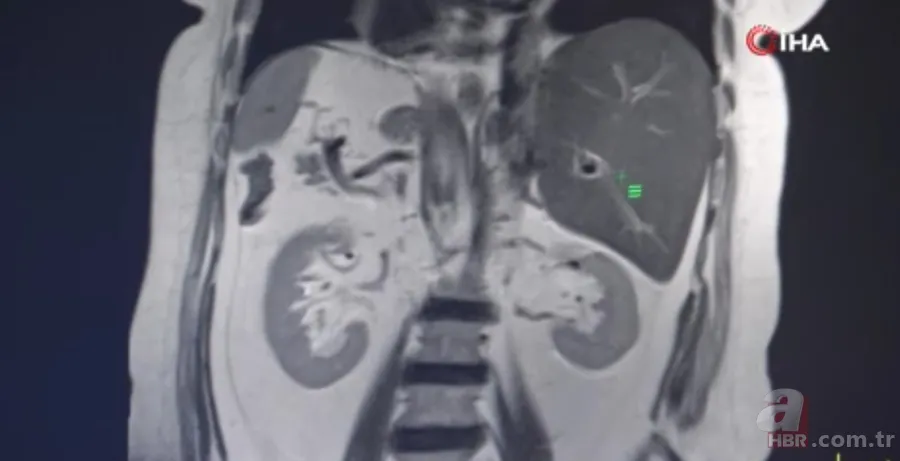

Son olarak Gaziantep Şehir Hastanesi'ne başvuran Evin Aslan'ın hastanede yapılan tetkikler sonucunda iç organlarının tamamının ters tarafta olduğu anlaşıldı. Kalp, mide, dalağı, göğüs ve karın bölgesinin sağında, karaciğer ve safra kesesinin ise solda olduğunu öğrenen Aslan, hayatının şokunu yaşadı.